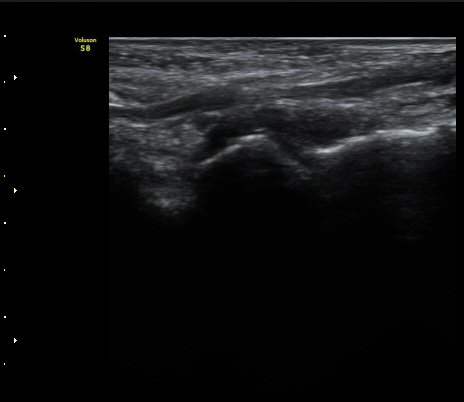

Àü¹æ°æ°ñºñ°ñÀδë¿Í Àü¹æ°Å°ñºñ°ñÀδë°Ë»ç ½Ã ƯÀÌ ¼Ò°ßÀ» º¸ÀÌÁö ¾ÊÀ½(»çÁø 8, 9).